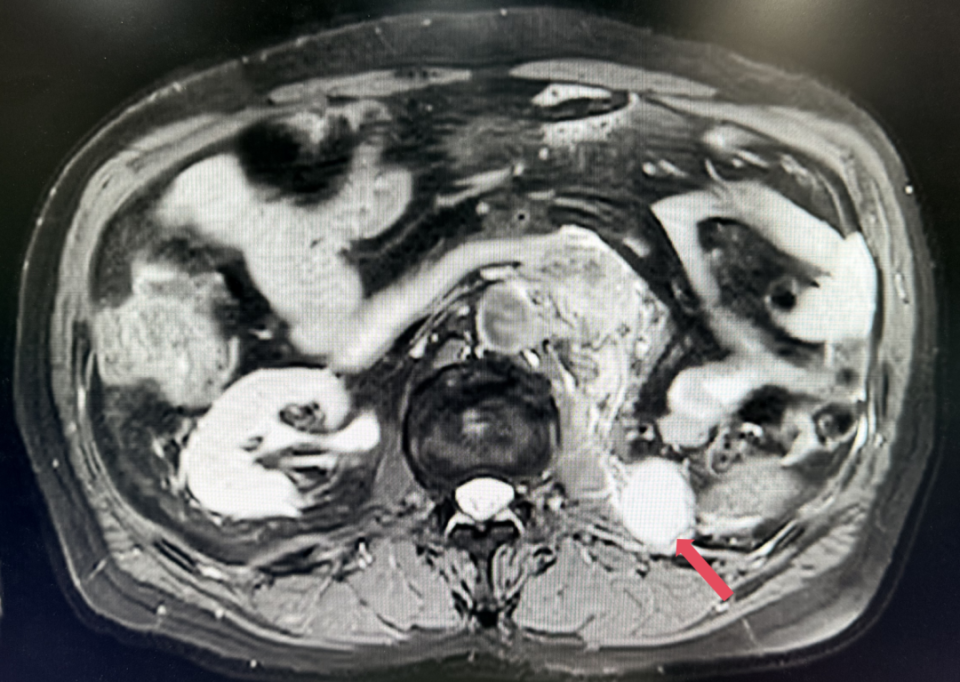

2023年1月,基线

2022年3月:患者因“左腰痛”复查。胸部CT提示双肺微小结节,较前未见明显变化;腹盆MR示:左侧腹膜后多发结节及肿块影,较大者约5.7cm*5.1cm;考虑患者诊断为转移性肾透明细胞癌,IV期,IMDC评分0分,低危组。予培唑帕尼一线治疗8个月,最佳疗效SD。